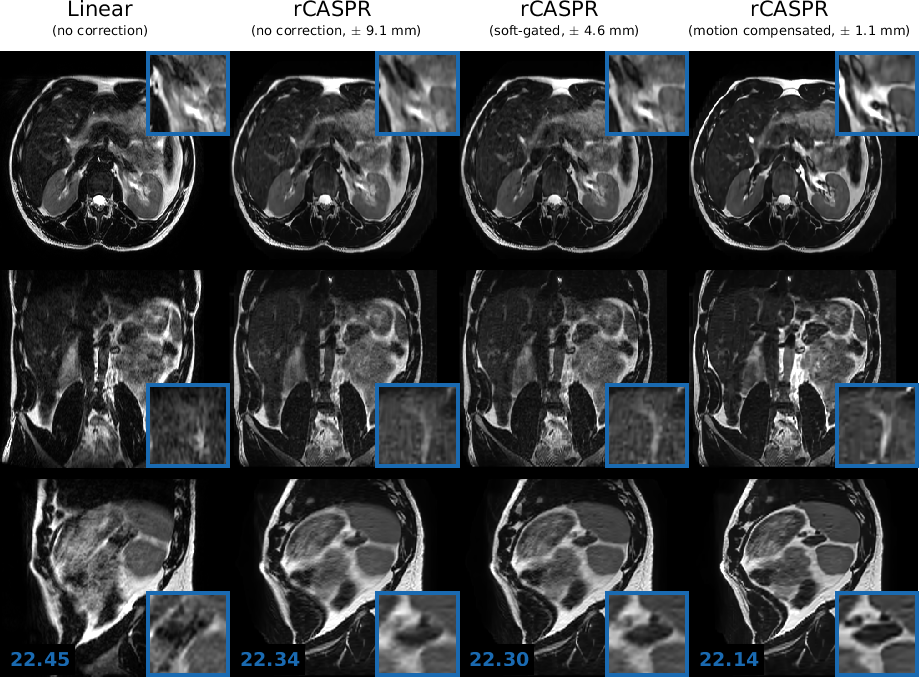

The comparison of image quality in two out of the eight volunteers are shown in Figures 8-7. The results of two other volunteers are shown in Supporting information I. Figure panels A-D show the linear, rCASPR, soft-gated rCASPR and motion compensated rCASPR reconstructions. Note that the soft-gated and motion compensated rCASPR are reconstructed at the exhale position. Zoom images of regions of interest are shown in blue boxes. Blue numbers at the left bottom display the gradient entropy calculated from the entire image. In general, image quality slightly increases when changing the sampling scheme from linear to rCASPR. The addition of soft-gating to rCASPR further increases the image quality. The largest improvement in image quality is observed when transitioning from no correction to the motion compensated image reconstruction.

Figure 7: Volunteer 2: Comparison of image quality in in T2subscript𝑇2T_{2}-w free-breathing 3D turbo spin echo scans for linear, rCASPR, soft-gated rCASPR and motion compensated rCASPR. For all the reconstructions the residual peak-to-peak motion was estimated using the 4D-MRI. For rCASPR the residual motion was ±9.1​m​mplus-or-minus9.1𝑚𝑚\pm 9.1\ mm, soft-gating rejected 50%percent5050\% of the data such that the residual motion was ±4.6​m​mplus-or-minus4.6𝑚𝑚\pm 4.6\ mm and motion compensation had residual intrabin motion of ±1.1​m​mplus-or-minus1.1𝑚𝑚\pm 1.1\ mm. The numbers in left bottom corner indicate the global gradient entropy. Blue boxes present zoomed regions. Acronyms: rCASPR = rewound cartesian acquisition with spiral profile ordering.

The groupwise average gradient entropy was 22.31±0.07plus-or-minus22.310.0722.31\pm 0.07 for linear, 22.20±0.09plus-or-minus22.200.0922.20\pm 0.09 for rCASPR, 22.14±0.10plus-or-minus22.140.1022.14\pm 0.10 for soft-gated rCASPR and 22.02±0.11plus-or-minus22.020.1122.02\pm 0.11 for motion compensated rCASPR. Supporting Information II shows a video of the motion compensated rCASPR reconstruction warped with the DVFs for all the volunteers.